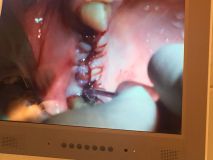

آموزش كاربردي چسب بافتي PeriAcryl كانادا همراه با جراحي زنده

جراح: آقاي دكتر عليرضا جهانگيرنيا

تاريخ: 25 دي 1394